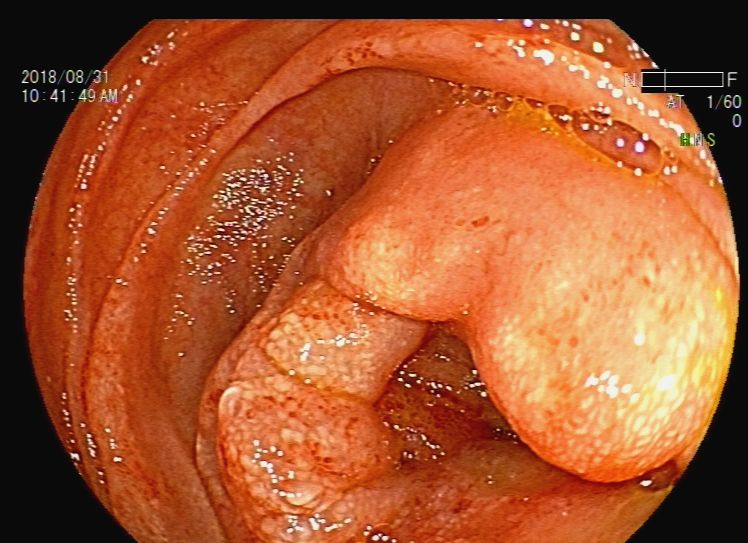

胃镜检查:反流性食管炎,胃内液体潴留,吻合口前区黏膜下隆起——考虑转移灶压迫,近端小肠梗阻(图9、图10、图11、图12、图13)。根据消化道造影及内镜检查结果,考虑梗阻部位在近端小肠,吻合口前区虽有较大的隆起灶,但是内镜通过可,暂不处理。

图12 胃镜检查见近端小肠梗阻

图13 胃镜检查见近端小肠梗阻

征得患者同意后,于2018年8月31日行内镜下肠道(小肠)支架置入术。术后梗阻症状缓解,患者可以进流食(图14、图15)。